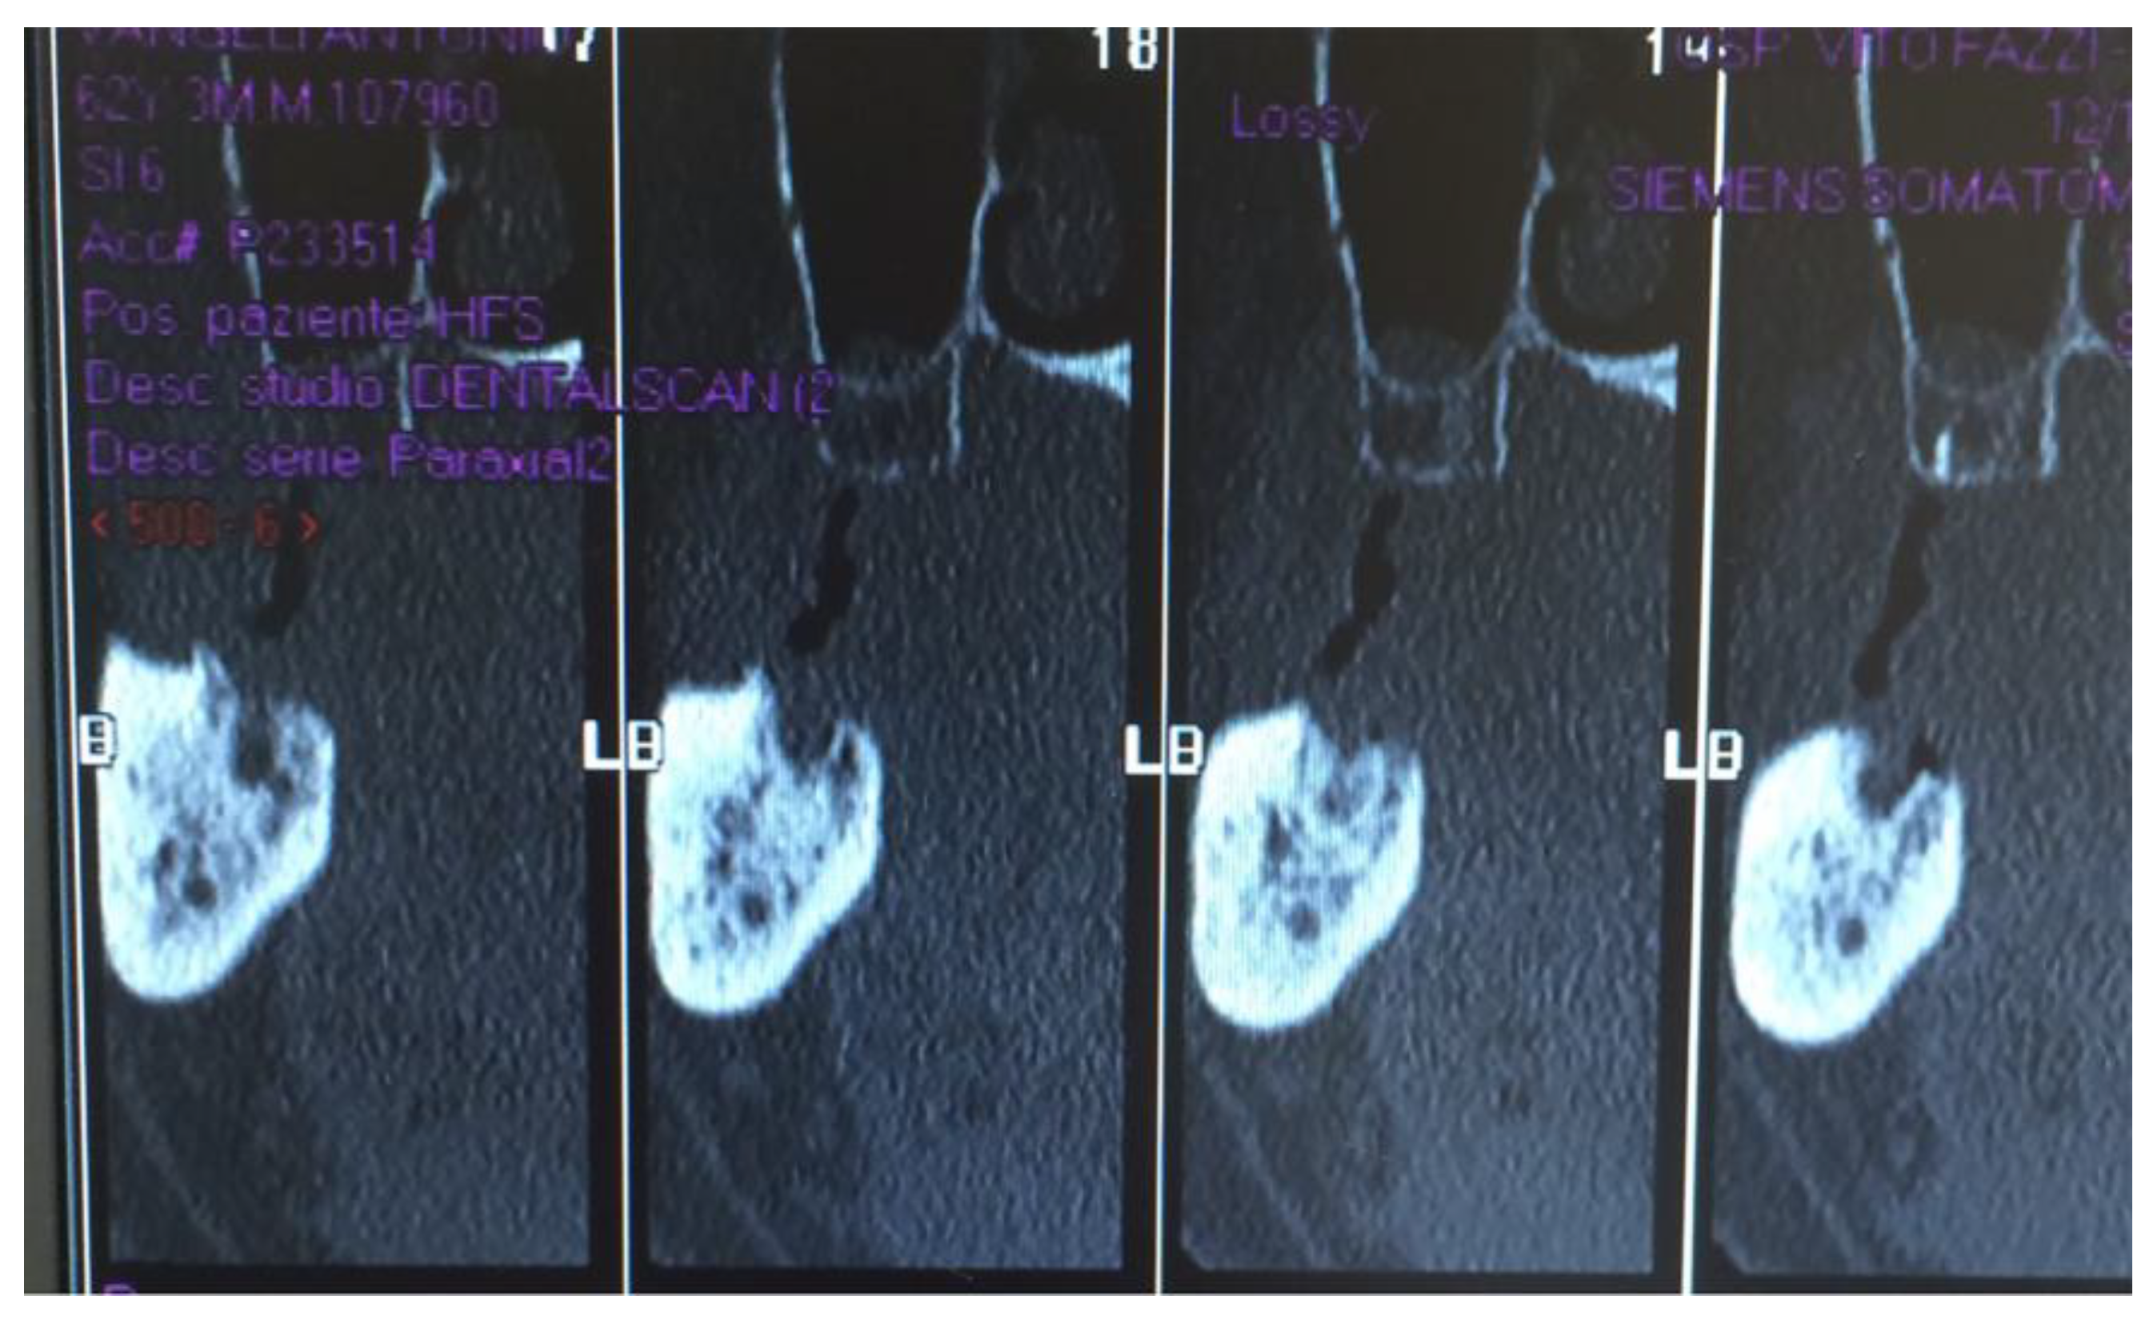

Figure 1, Figure 2, Figure 3, Figure 4, Figure 5, Figure 6 and Figure 7 show the progress of treatment in one of the patients of the test group. In Figure 3 reduction of the medullar space is visible, that may create a chronic ischemic area susceptible to necrosis.

Figure 3.

Pre-operative CBCT of the MRONJ patient, showing a reduction in the medullar space.